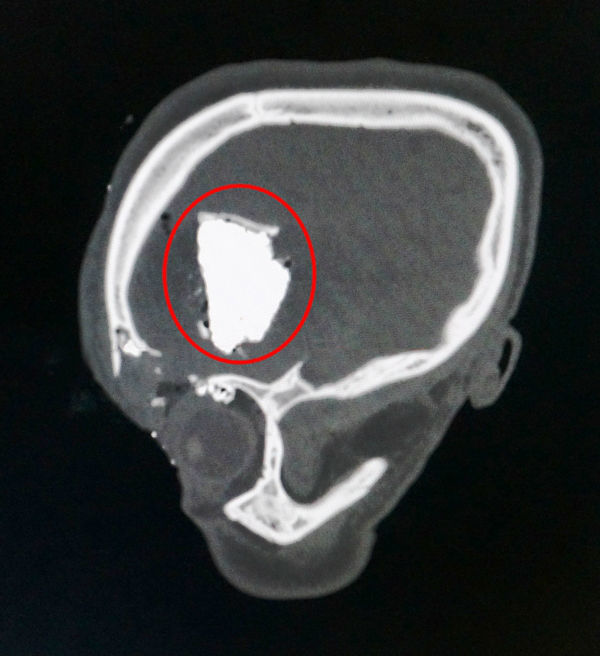

Mảnh lưỡi cưa ghim sâu vào đầu anh Long |

Qua thăm khám, bác sĩ nhận thấy bệnh nhân bị vỡ xương trán trái, vỡ trần hốc mắt trái. Có dị vật kích thước khoảng 28 x 43 mm ghim sâu vào vùng não trái, xuất huyết não và tụ khí nội sọ quanh dị vật.